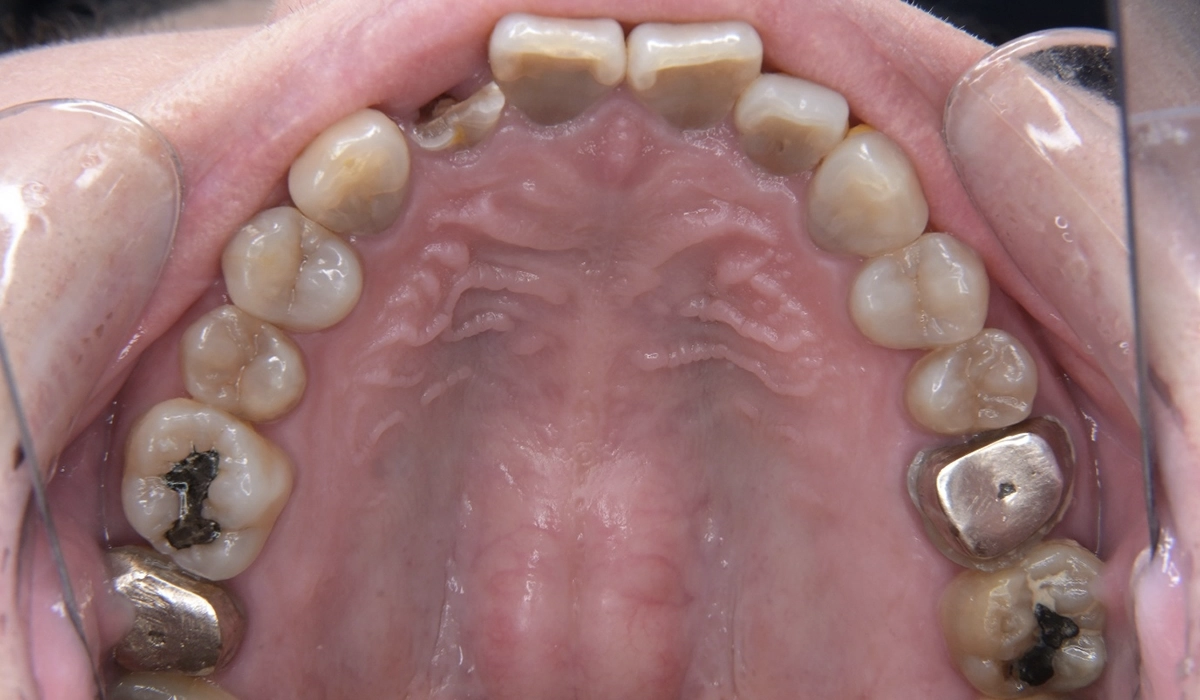

こちらが術前の口腔内写真になります。

問題点としては前歯部、臼歯部で進行したカリエスおよび前歯部歯肉増殖症、広範型慢性歯周炎StageⅡ GradeAが挙げられます。本症例では前歯部の審美性の回復について患者様との話し合いのうえセラミック修復による治療を選択しました。